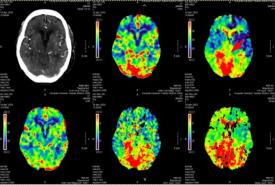

Defying All Odds: Successful Thrombolysis in a Nonagenarian with Posterior Circulation Infarct

Case Report 27 Jan, 2025

Tengku Mohamed Izam Tengku Kamalden

• Read more about Tengku Mohamed Izam Tengku Kamalden

Khairunnisak Misron

• Read more about Khairunnisak Misron

Rahmat Haron

• Read more about Rahmat Haron